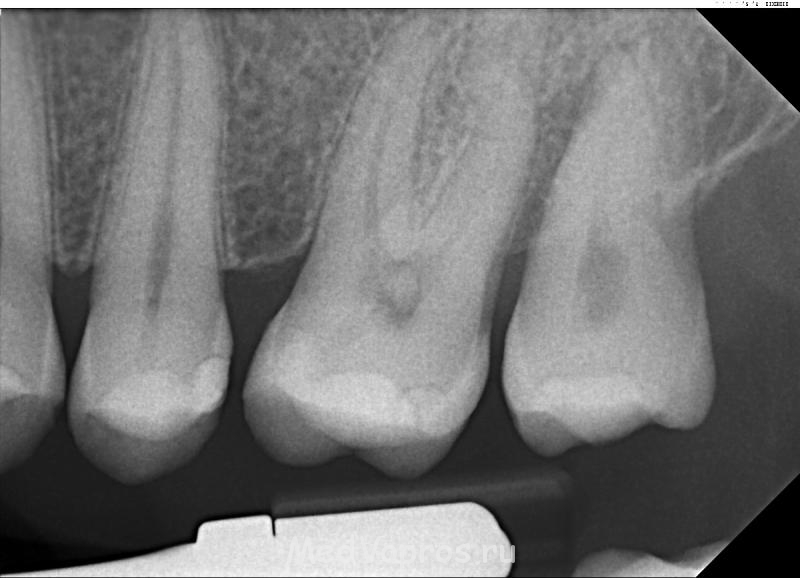

Здравствуйте. У меня болит левая-верхняя часть. Последний зуб. Третий слева зуб вырвали лет 15 назад. Острой боли нет, но кусать не могу. На холодное и горячее не реагирует. Чувствую, что щека немного опухла. Боль длится уже четыре дня, но постепенно спадает.

Кариеса нет. Инфекции нет. Врач попался како-то странный, чего делать сказать не может. Говорит, что десна стерлась. что зуб расшатан (class 2-3). Чего делать, не сказал. Толи вырывать, толи хирургию, а может еще чего. Вот мой ренген. http://i46.tinypic (dot) com/nvqohx.jpg

- Ренген - Med - tooth 2012 Aug 28.JPG (137.92 КБ) 938 просмотров